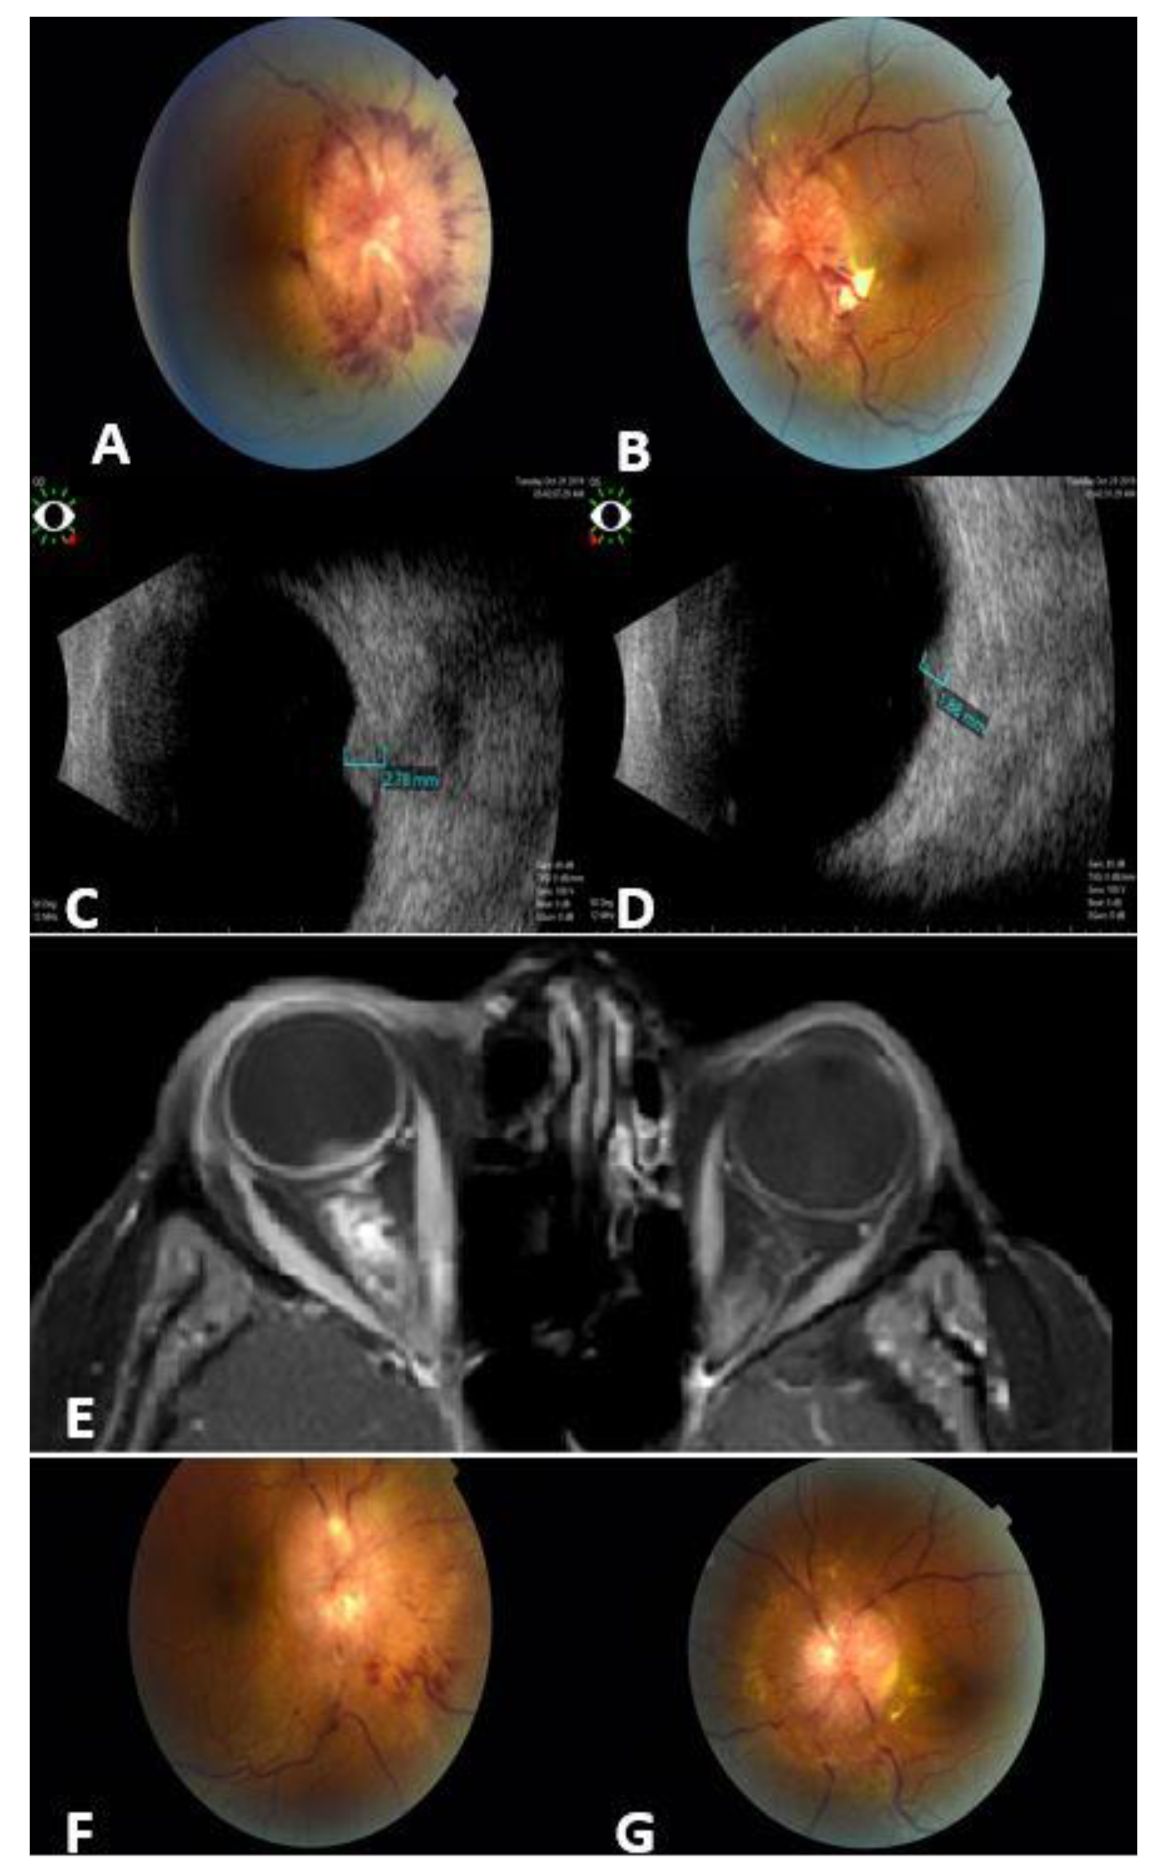

Figure 2. A 43-year-old female with metastatic breast cancer to the optic nerves. Fundus photos for the right (A) and left (B) eyes show bilateral infiltrates around the optic nerves, more prominent in the right eye (A). Ocular B-scan photos show clearly the hyperechoic masses over the right (C) and left (D) optic nerves. Orbit MRI Axial T1-weighted scan with contrast (E) shows thickening of the optic nerve sheath that extends to the optic nerve head (more prominent on the right side), irregular outline, and stranding of surrounding fat planes. Fundus photos for the same patient 3 months post orbit EBRT: major regression in optic nerve infiltrates in both eyes: right (F); left (G).